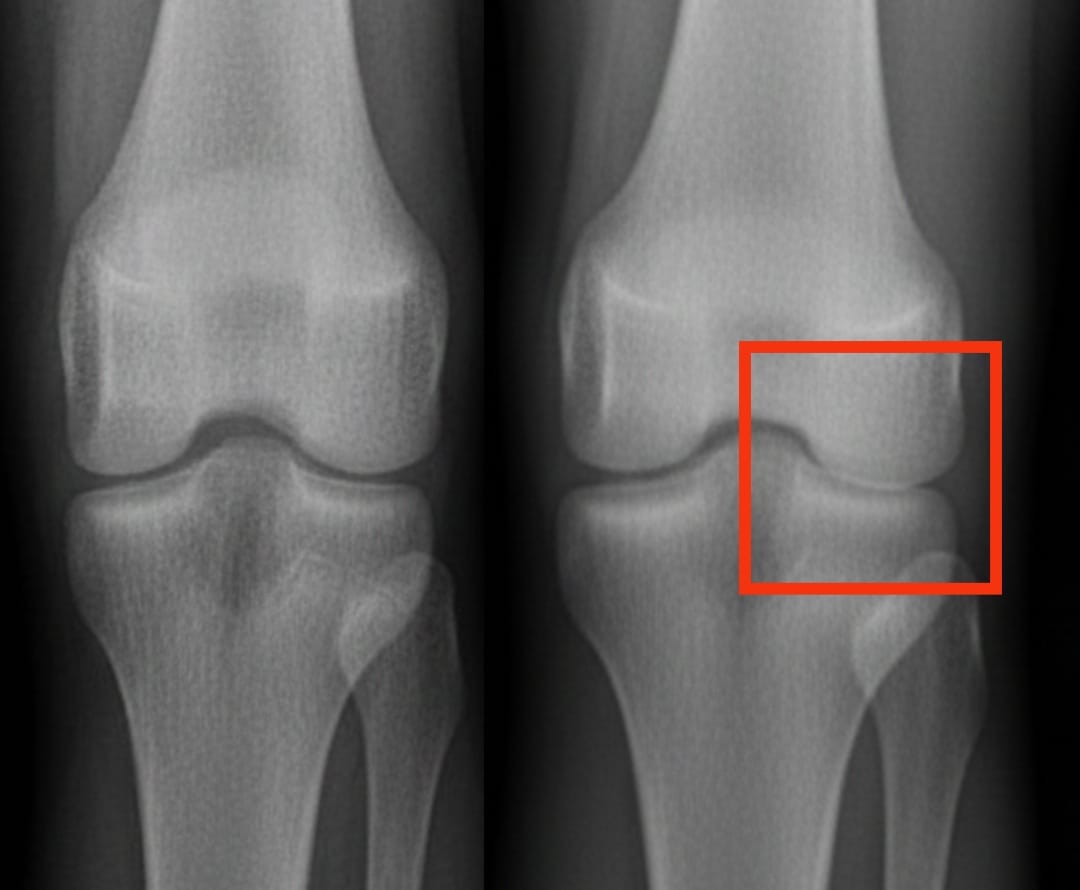

膝关节炎影响着全球数亿人。其特征是软骨逐渐磨损,导致疼痛和活动困难。在众多治疗方案中,血小板富血浆注射越来越受到关注。这种疗法利用患者自身的血液,通过浓缩血小板来促进组织修复并减少炎症。

最近的一项分析比较了血小板富血浆与其他常见注射疗法(透明质酸、皮质类固醇和生理盐水安慰剂)的疗效。结果显示,血小板富血浆在六个月后显著改善疼痛和关节活动度,且效果可持续一年。这些改善比透明质酸或皮质类固醇更为显著,远超安慰剂的效果。